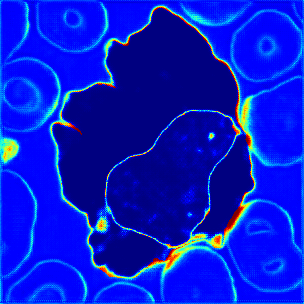

Figure 7: Visualization results of ATA-Module’s Attention Map: (a) Input image. (b-e) Attention map.

4.3.3 Visualization of ATA-Module

The attention maps of ATA-Module in AML-Net are visualized in Figure 7. When we select a cytoplasmic pixel as a reference, the cytoplasmic regions with high similarity are highlighted in red as shown in Figure 7. As shown in Figure 7, the attention map will respond only to cell nucleus and the other classes are blue with low similarity when cell nucleus is selected as a reference. In addition, as shown in Figure 7, when a pixel of an red blood cell which is a part of the background pixel is selected, only the similar red blood cells are reacted to not the entire background. Therefore, in Figure 7, it can be confirmed that red blood cells are not reacted when the pixels of the background other than red blood cells are selected. These results show that ATA-Module can enhance the similarity not only among the three classes; cytoplasm, cell nucleus and background, but also between red blood cells and other parts of the background. Based on these attention maps created from the discriminator, efficient leakage to the generator is performed.